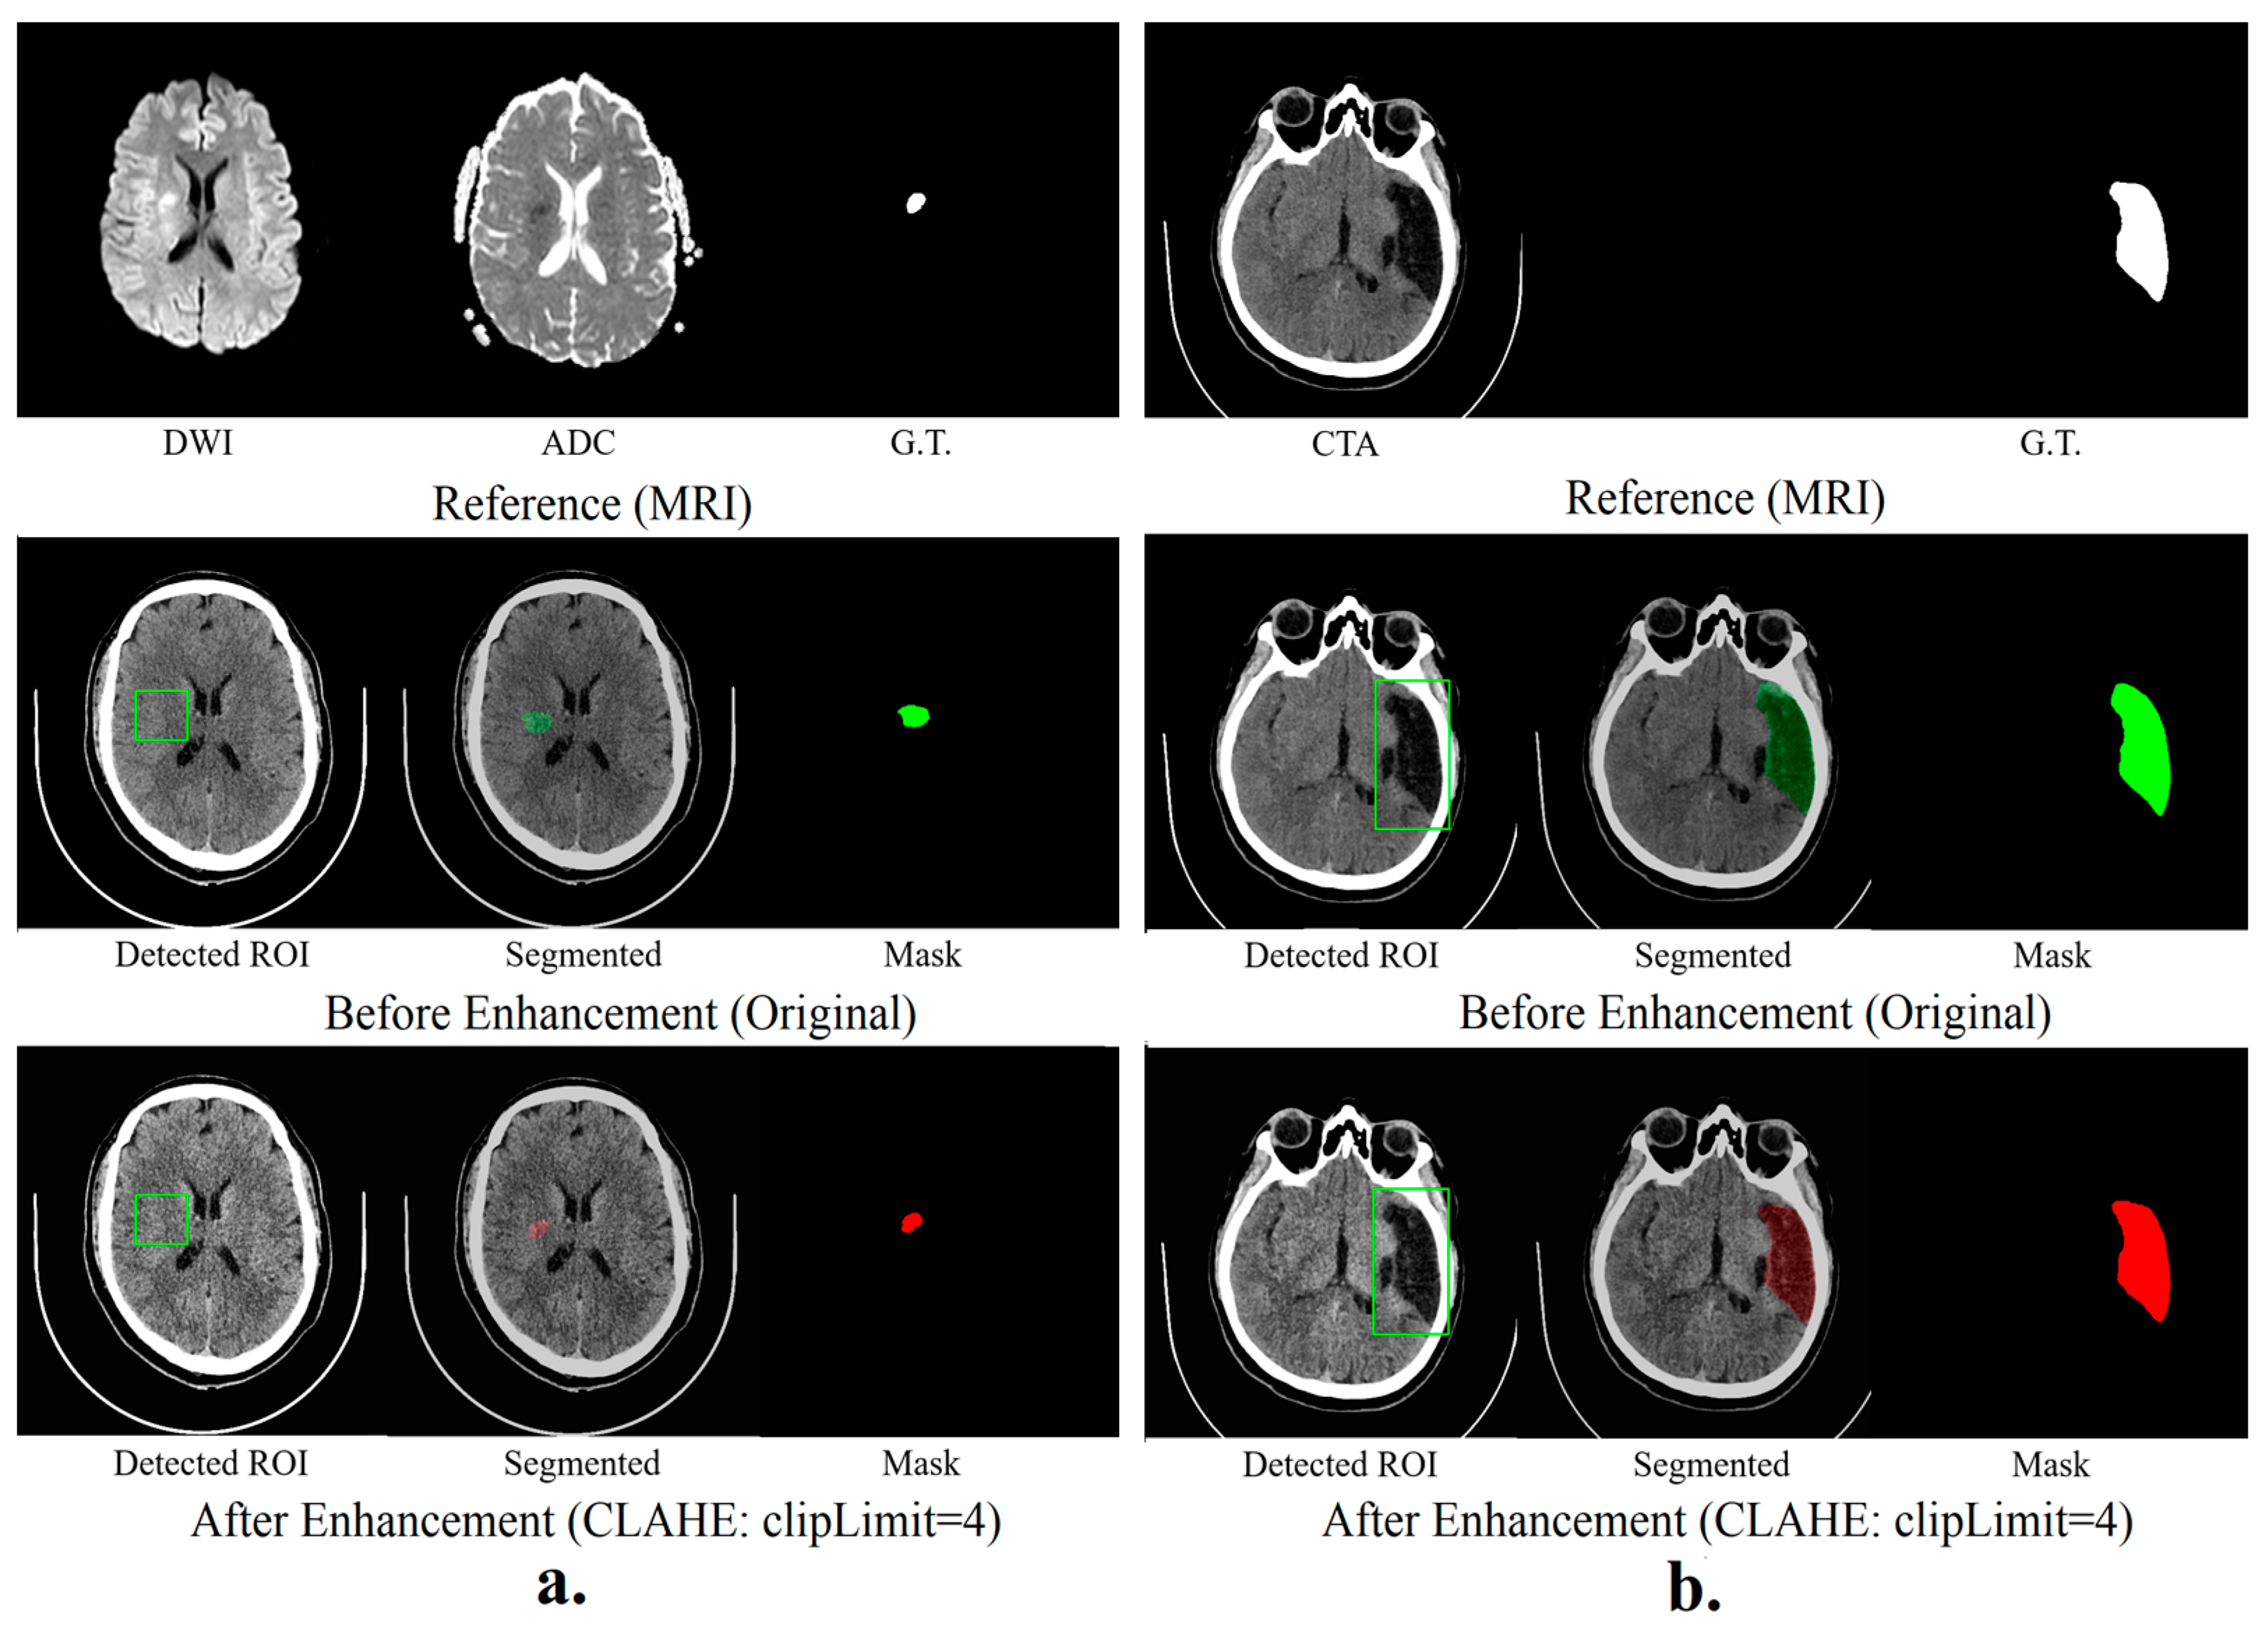

Results in Figure 3 reveal that the hybrid segmentation method, especially with SPEM-enhanced data, excels in accurately identifying stroke lesions in CT scans. The noticeable boost in Dice similarity coefficients (DSCs) for hyper-acute, acute, and sub-acute strokes highlights the significant role of image enhancement in increasing lesion detection accuracy for these stroke types. On the other hand, for chronic strokes, the unenhanced original data yielded marginally superior outcomes, indicating that SPEM’s effectiveness may differ based on the stroke’s nature and features.

Figure 3. Hybrid segmentation models (a) show the results of hyper-acute segmentation, and (b) show the chronic segmentation results.